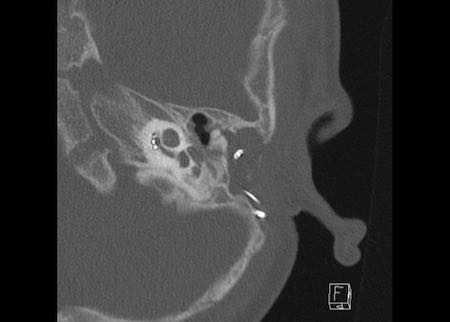

Bé trai 8 tuổi được cấy ghép ốc tai hai bên. Vị trí bình thường ở tai phải.

Một điện cực được đặt đúng vị trí với tất cả các kênh của nó, hiện ra như một chuỗi hạt, nằm trong ốc tai và xoắn lên theo hướng đỉnh ốc tai.

Tiếp tục xem hình ảnh của tai trái.